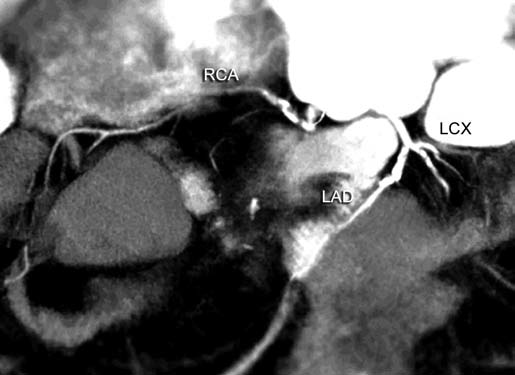

Coronary stenosis (Fig. 4) can be detected efectively.

Degree of stenosis is categorized as minimal, mild, moderate

and marked. Diagnostic accuracy falls as one goes down

to distal part of vessel as caliber decreases. Ostial stenosis

LM and right coronary artery (RCA) can be picked. Rarely

detection of ostial lesion may be the sole purpose of CT, after

an inadequate evaluation of ostia on catheter angiogram.

Even in CT, evaluation of ostial lesion is hard as compared

to diagnosis of segmental stenosis.